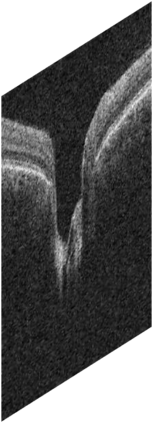

Fairness in artificial intelligence models has gained significantly more attention in recent years, especially in the area of medicine, as fairness in medical models is critical to people's well-being and lives. High-quality medical fairness datasets are needed to promote fairness learning research. Existing medical fairness datasets are all for classification tasks, and no fairness datasets are available for medical segmentation, while medical segmentation is an equally important clinical task as classifications, which can provide detailed spatial information on organ abnormalities ready to be assessed by clinicians. In this paper, we propose the first fairness dataset for medical segmentation named Harvard-FairSeg with 10,000 subject samples. In addition, we propose a fair error-bound scaling approach to reweight the loss function with the upper error-bound in each identity group, using the segment anything model (SAM). We anticipate that the segmentation performance equity can be improved by explicitly tackling the hard cases with high training errors in each identity group. To facilitate fair comparisons, we utilize a novel equity-scaled segmentation performance metric to compare segmentation metrics in the context of fairness, such as the equity-scaled Dice coefficient. Through comprehensive experiments, we demonstrate that our fair error-bound scaling approach either has superior or comparable fairness performance to the state-of-the-art fairness learning models. The dataset and code are publicly accessible via https://ophai.hms.harvard.edu/harvard-fairseg10k.